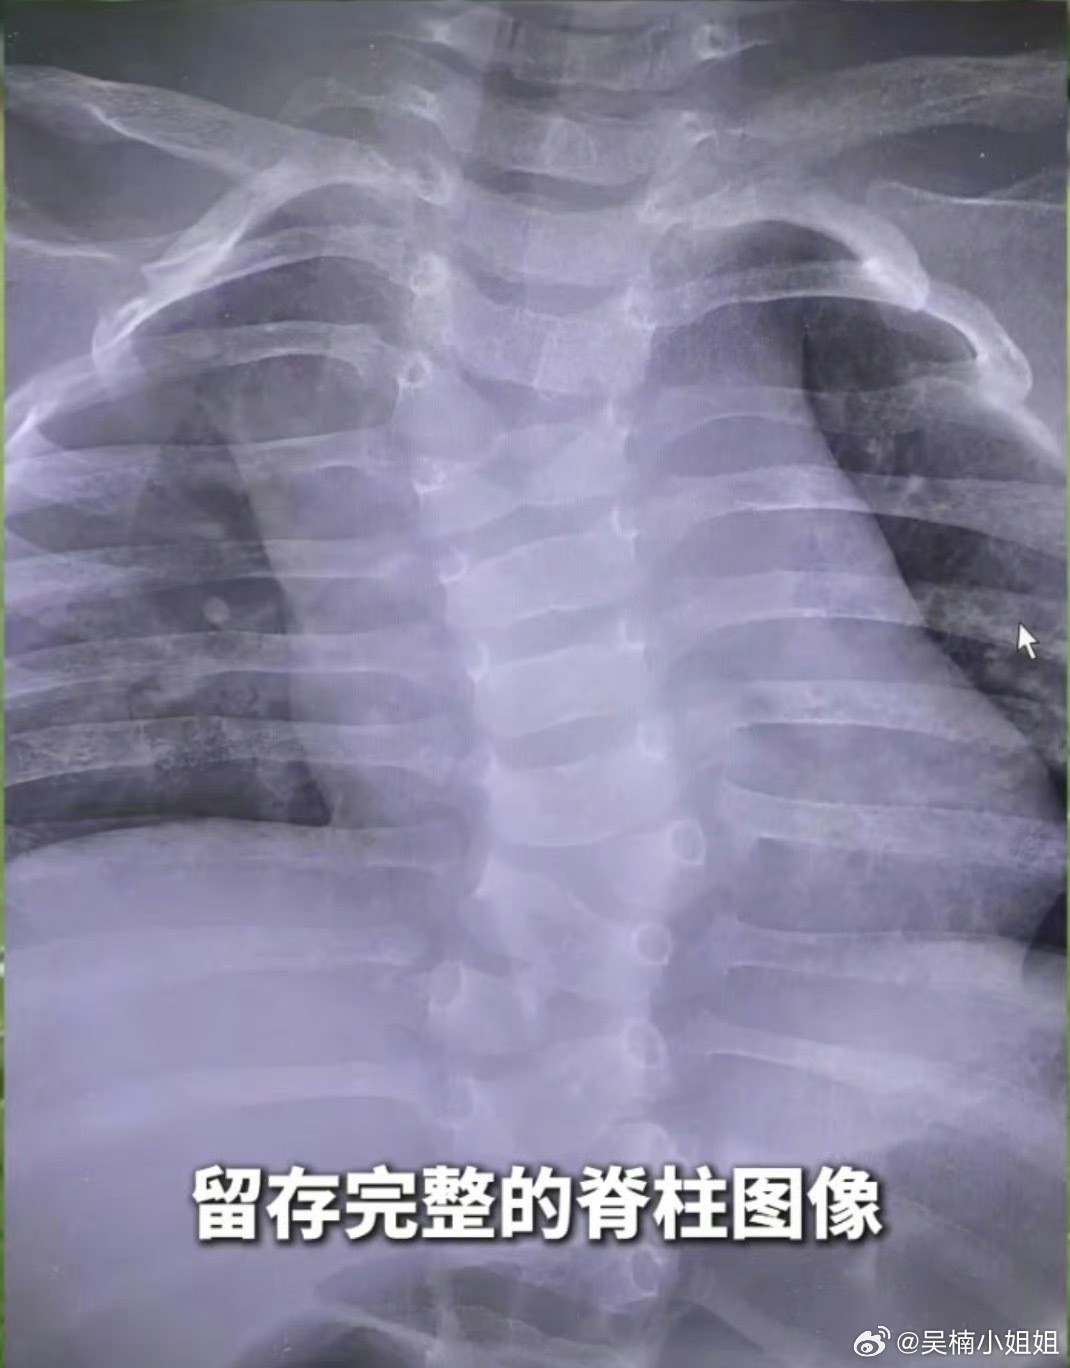

官方通报产检正常娃出生却先天畸形产检就是为了追求孩子健康和做好预防工作,结果这么

官方通报产检正常娃出生却先天畸形产检就是为了追求孩子健康和做好预防工作,结果这么大的问题没检查出来你连这个都要骗的话,还有什么是不能骗的